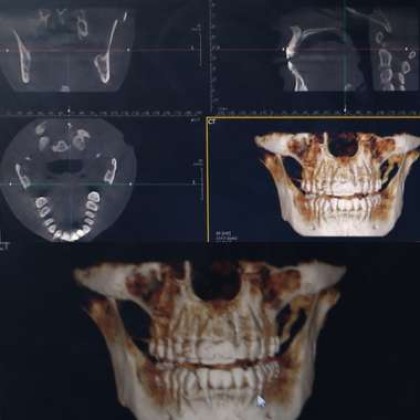

Bone Loss in Teeth

Do you have one or several missing teeth? Do you have periodontitis...

Root Canal (Endodontic) Treatment

Root canal treatment is the removal of the soft tissue in the centre...